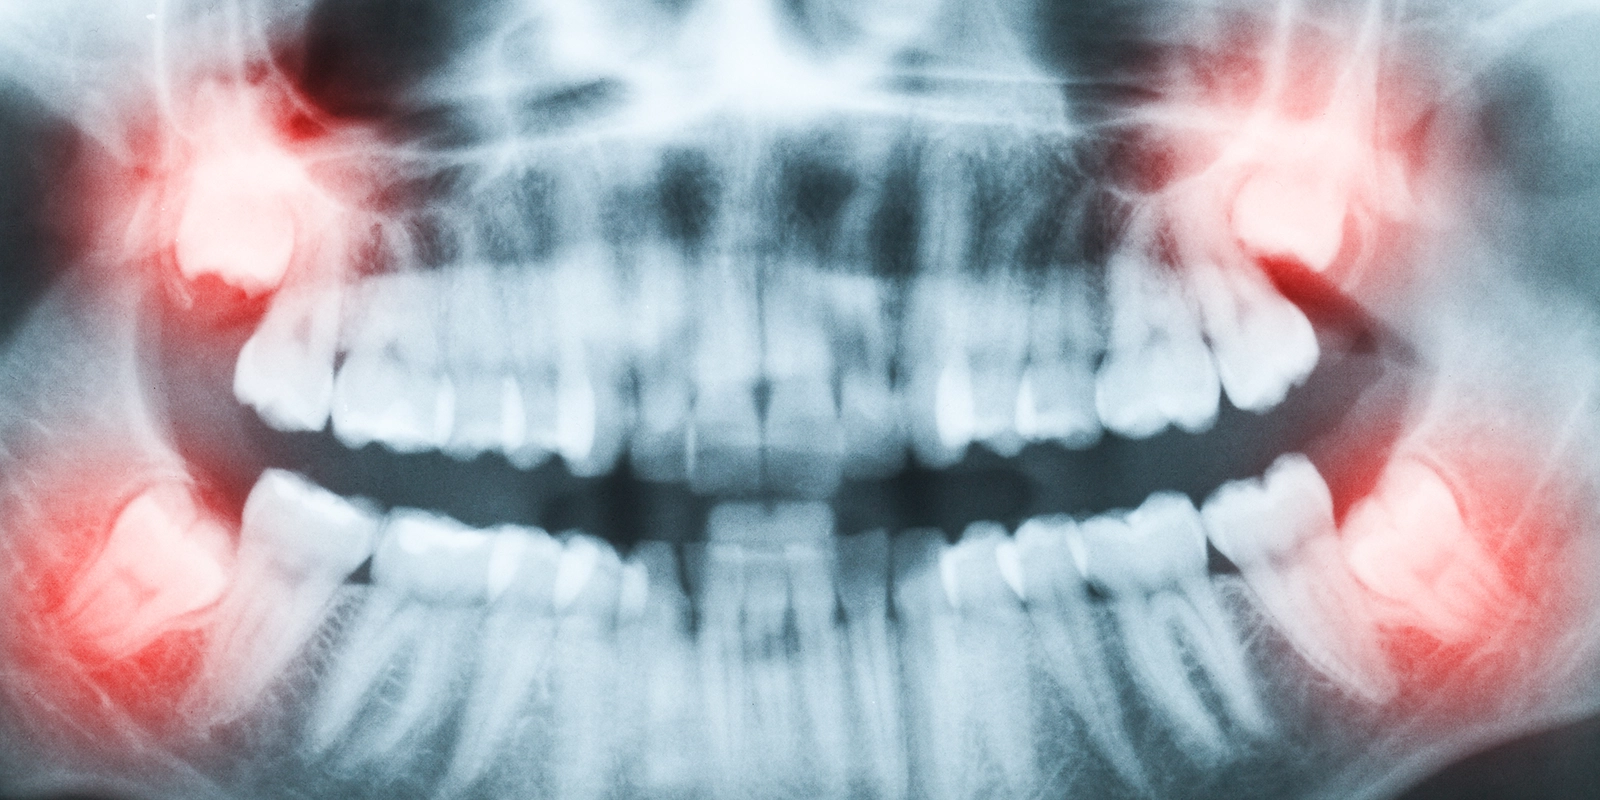

人類の進化の過程で、顎の骨が小さくなったにもかかわらず、歯の本数は変わらなかったため、最も奥に生える親知らずのスペースが不足しやすくなりました。その結果、親知らずは正常に生えずに、傾いたり、一部だけが顔を出したり、完全に埋まったままだったりすることが多くなっています。

親知らずの生え方は、「完全萌出」「部分萌出」「完全埋伏」の3つに分類されます。完全萌出は、親知らずが正常に生えて、上下でしっかり噛み合っている状態です。部分萌出は、親知らずの一部だけが歯茎から出ている状態で、残りは歯茎や骨に覆われています。完全埋伏は、親知らずが完全に骨の中に埋まったままの状態です。

親知らずが正常に生えず、傾いたり埋まったりしていると、様々な問題が生じます。最も多い問題は「智歯周囲炎」です。部分萌出の親知らずでは、歯と歯茎の間に深いポケットができ、そこに食べ物の残りやプラークが溜まります。

横向きに生えた親知らずは、手前の第二大臼歯を押す力を加えるため、歯並びに影響を与えることがあります。また、親知らずと第二大臼歯の間に食べ物が詰まりやすく、両方の歯が虫歯になるリスクが高まります。特に、親知らずが第二大臼歯の根に接触している場合、第二大臼歯に「歯根吸収」という現象が起こり、歯の根が溶けてしまうこともあります。

完全に埋まっている親知らずでも、周囲に「含歯性嚢胞」という袋状の病変を形成することがあります。嚢胞が大きくなると、顎の骨を圧迫して骨を溶かし、顎の骨折のリスクを高めます。